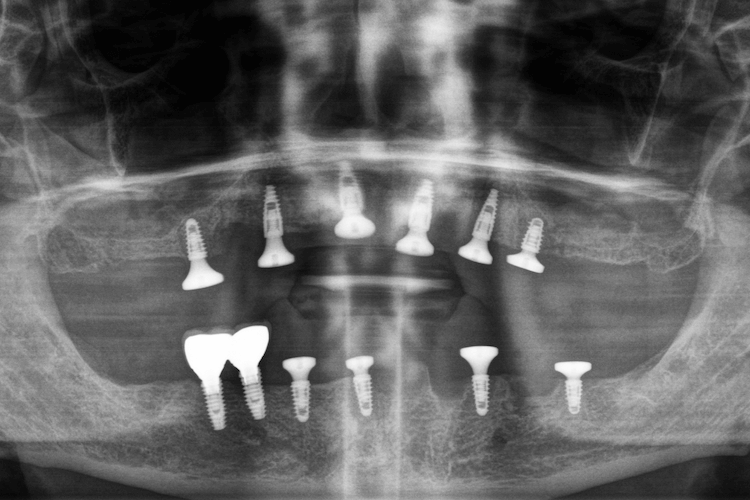

Під час огляду та діагностики нижньої щелепи було виявлено захворювання тканин пародонту в області опорних зубів мостоподібного протезу, 2 імплантати виробництва Південної Кореї з правого боку в області зубів 5 та 6, а також, ретинований "зуб мудрості" з правого боку. Додатково, пацієнт повідомив що не може використовувати знімні протези через посилений блювотний рефлекс та загальний дискомфорт в експлуатації подібних конструкцій.

- Відновити зубний ряд на верхній щелепі за протоколом All-on-6.

- Встановити 4 імплантати на нижній щелепі, які слугуватимуть опорами для мостоподібних конструкцій в області відсутніх зубів.

- В перспективі, після інтеграції нижніх 4 імплантів, підв’язати два імпланти (які вже встановлені) до суцільнолитої ортопедичної конструкції.

- Протезування виконати суцільнолитими ортопедичними протезами з діоксиду цирконію, з посиленням конструкції металевою балкою.